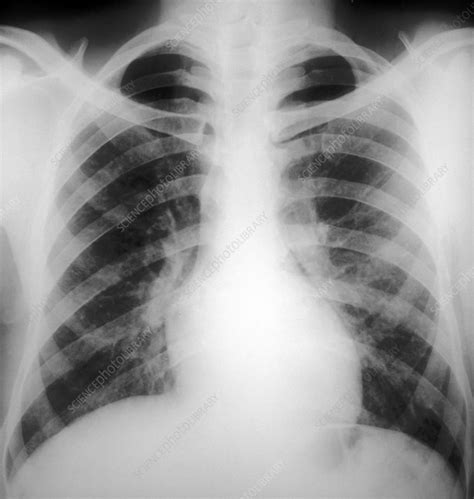

Typical bronchitis x-ray chest findings in acute bronchitis might not reveal any significant abnormalities. The lungs may appear clear, even in the presence of inflammation. This is because acute bronchitis primarily affects the airways, which are not always clearly visible on a standard x-ray.

In acute bronchitis, a chest x-ray may appear normal, even in the presence of inflammation. This is because the primary site of inflammation, the bronchial tubes, may not be clearly visible on a standard x-ray.